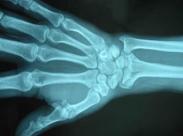

橈骨下端骨折

橈骨下端骨折是指距橈骨下端關節面3厘米以內的骨折,這個部位是松質骨與密質骨的交界處,為解剖薄弱處,一旦遭受外力,容易骨折,常伴橈腕關節及下尺橈關節的損壞。橈骨下端構成橈腕關節,其關節面向掌側傾斜10-15°,向尺側傾斜20-25°,當骨折發生移位時,其關節面角度發生改變,因此可形成常見的伸直型骨折和屈曲型骨折。橈骨下端骨折極為常見,多見于老年婦女、兒童及青年。